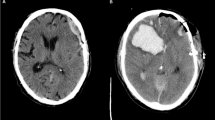

Method: A 3-year-old boy was admitted to our clinic with paraplegia 24 h after falling from a height of about 5 meters. Investigation revealed an acute spinal subdural haematoma.

Conclusion: MRI is the most valuable diagnostic method. In each case diagnosed as ASSH, prompt evacuation should be performed before irreversible neurological damage occurs.